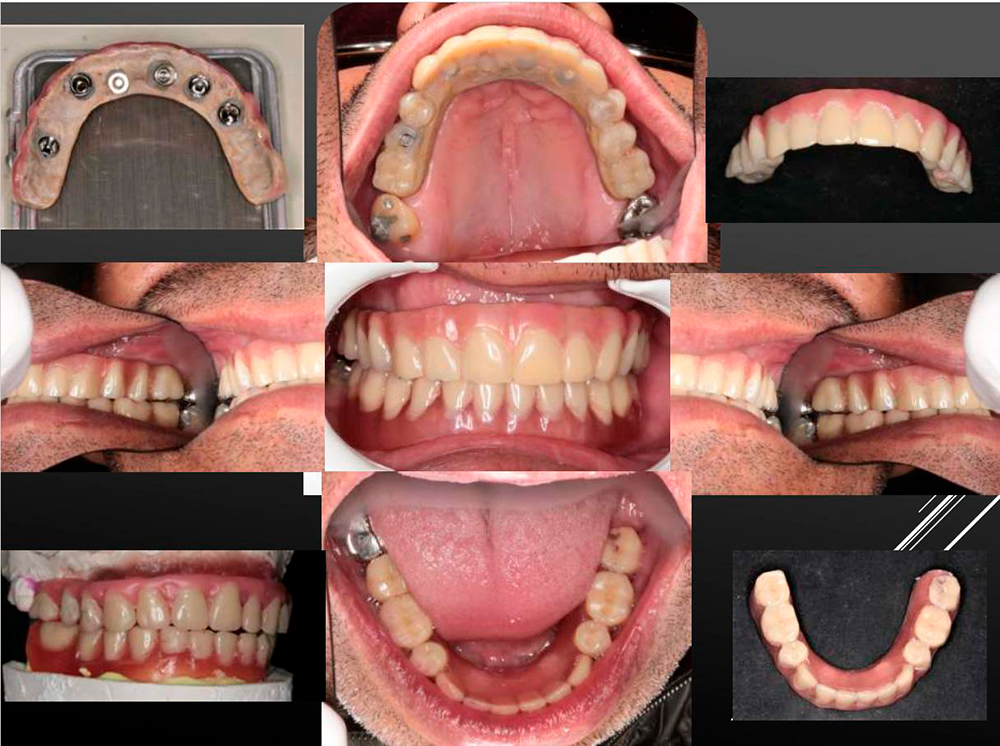

All-On-6: Entire Arch Restoration with DSI Next-Gen Multi-Unit

The wide range of DSI prosthetic parts gives the surgeon the freedom to find the ideal solution for every case.

Here is a perfect example - the removable denture based on the Premium Spiral Implants with a strong multi-unit anchoring the full upper overdenture.

The lower jaw is reconstructed by using the Lock-attachment system. Full restoration was created in a previos visit of the patient